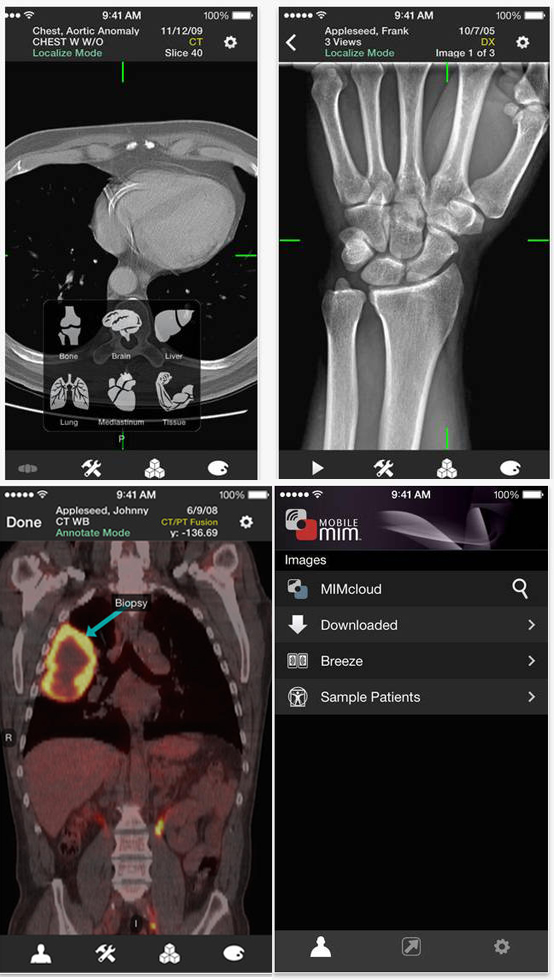

Mobile MIM

Mobile MIM 软件程序用于浏览各类医学影像类图像,包括SPECT, PET, CT, MRI, X-ray和Ultrasound等专业图像。遵照规定,该程序不能用于乳房X线照相。它界面强大、具有实时展现多模态医学图像、3D深度MIP视频、窗口自适应图像大小、测量标注PET图像等功能。 它是FDA批准的首家医疗影像类APP,2008年就亮相Apple的APP Store,2011年,FDA官方授权其通过510(k)规定,能被FDA批准的很大原因是应用的成像性强大,能解决不同手机展示终端的图片亮度问题。在医生对比两幅图像的时候,照片亮度不会干扰医生观察,而且插入很多指引性动态说明。 下载APP免费,但上传图像到MIM云端或下载到移动APP上浏览需要收费,且通过网页版MIM读图器需要收费。有按月收费也有按次收取。Mobile MIM只作为工作站的后备力量,但不能替代影像工作站。